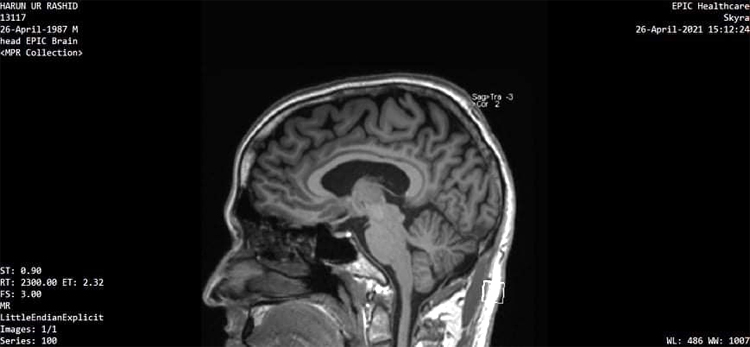

হারুনুর রশিদ অভিযোগ করেছেন, এমআরআই পরীক্ষায় তার মাথায় নিউরো চিপ শনাক্ত হয়েছে

jagonews24এই এমআরআই পরীক্ষার রিপোর্ট দেখিয়ে হারুন বলছেন, তার মাথায় নিউরো চিপ শনাক্ত হয়েছে

সম্প্রতি যুক্তরাষ্ট্র থেকে আনা লো ফ্রিকোয়েন্সির মাইক্রোচিপ শনাক্তকারী ডিভাইস দিয়ে মাথায় নিউরো চিপের অস্তিত্ব শনাক্ত করা গেছে দাবি করে হারুন বলেন, এ শনাক্তকরণ ডিভাইসটি AGPTek CC308+ Anti-Spy Signal Bug RF Detector মডেলের। বিদেশি একজন চিকিৎসকের পরামর্শ অনুযায়ী একাধিকবারের চেষ্টায় এমআরআই টেস্টে মাথায় ওই চিপ ধরা পড়ে।

হারুন দাবি করেছেন, তার এমআরআই পরীক্ষা চট্টগ্রামের এপিক হেলথ কেয়ার লিমিটেডে করেছেন এবং সেই টেস্টেই মাথায় ডিভাইস শনাক্ত হয়েছে। এ বিষয়ে ওই হাসপাতালে যোগাযোগ করলে প্রতিষ্ঠানটির জনসংযোগ কর্মকর্তা (পিআরও) কাউসার আলম জাগো নিউজকে বলেন, হাসপাতালের সংরক্ষিত তথ্যভান্ডারে হারুনুর রশিদ নামে ওই রোগীর এমআরআই পরীক্ষার ‘সঠিকতা’ রয়েছে। হাসপাতালের পরিচালক ডা. এনামুল হকের রেফারেন্স তিনি এমআরআই করান এবং তার রিপোর্ট পর্যালোচনা লেখেন এমআরআই বিশেষজ্ঞ প্রফেসর ডা. দিদারুল আলম।